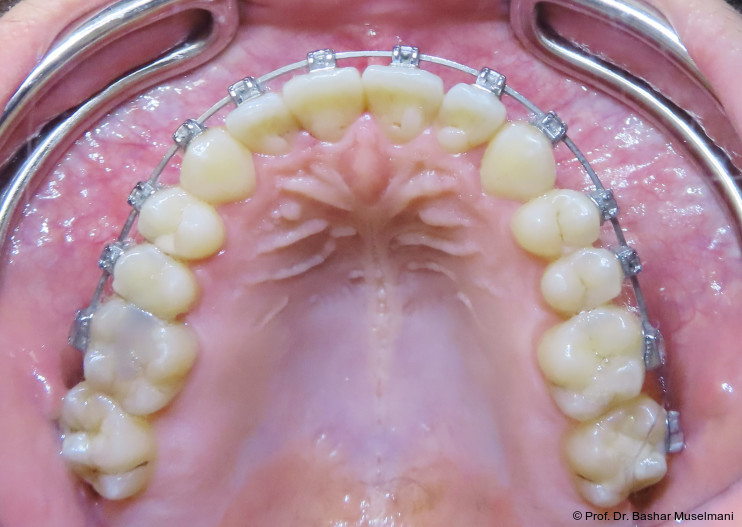

Die Abbildungen 1 bis 3 zeigen die initiale klinische und radiologische Ausgangssituation.

Apparative Versorgung

Die Behandlung erfolgte mittels einer festsitzenden Multibracketapparatur unter Verwendung passiver selbstligierender Brackets (Damon Ultima System) im Ober- und Unterkiefer.

Zu Beginn der Nivellierungsphase wurden in beiden Kiefern 0.013" CuNiTi-Bögen eingesetzt (Abb. 4a–e).